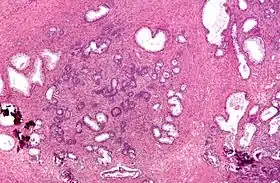

![]() Micrograph of a transurethral resection of the prostate (TURP) specimen, showing BPH (nodular hyperplasia of the prostate) – left-of-center in image. H&E stain. | |